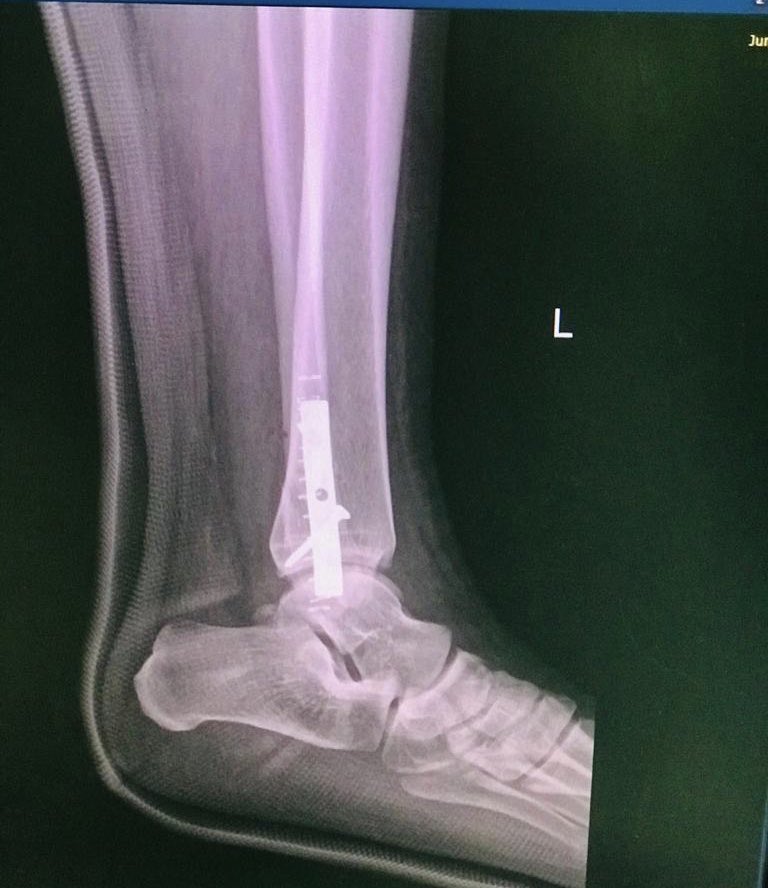

٣-ذهبت للموعد و اعادو لي الإشاعة و ذكر لي الجراح ان الكسر موجود و عندنا خيارين واحد منهم تجلس على الجبس بدون عملية و الثاني نعمل عملية نثبت الكسر و كل الحلين صحيح و فترت عدم وقوفك نفسها ٦-٨ اسابع بسبب قطع اربطه الكاحل

قلت له انت ايش رأيك قال لي عملية و لكن انت قرر فقلت اذن عمليه

٥-تمت العمليه و لله الحمد و شكرا و جزى الله خيراً لكل من حملني و انزلني و رافقني من سريري و حتى سرير غرفة العمليات و لفريق التخدير و فريق جراحة العظام

أخيرا الشكر لله ثم لأخي الدكتور وائل طه إستشاري جراحة العظام و الإصابات على ماقام به و لا أملك له إلا الدعاء و من المفارقات الجميله أن الدكتورة أفنان الفريدي التي ساعدت في العملية هي إحدى أميز خريجات كليتنا و تشرفت أني درستها في يوم ما و بحول الله ستكون إستشارية جراحة عظام كبيرة